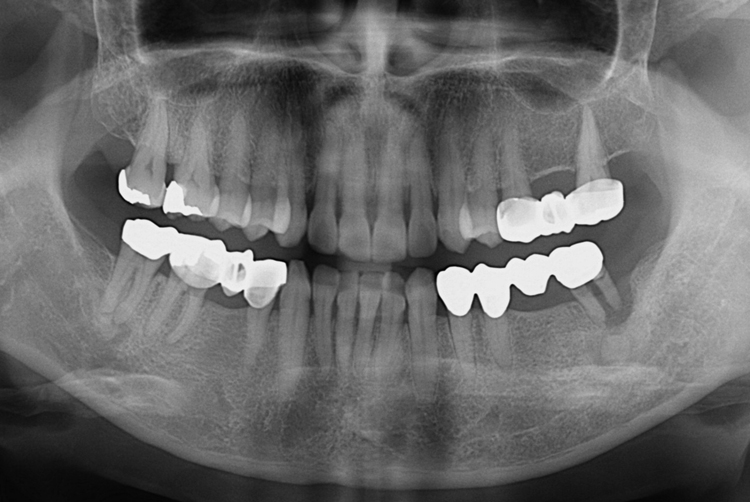

치료사례

세종치과의 진심 어린 치료는 결과로 말합니다.

실제 내원하신 환자분들의 치료 전·후 사례를 확인해보세요.

모든 치료사례 전후사진은 환자분의 동의하에 촬영되었습니다.

모든사진은 동일 환자분의 전후모습을 촬영하였으며, 사진의 밝기조절 외에 임의 수정이 없음을 알려드립니다.